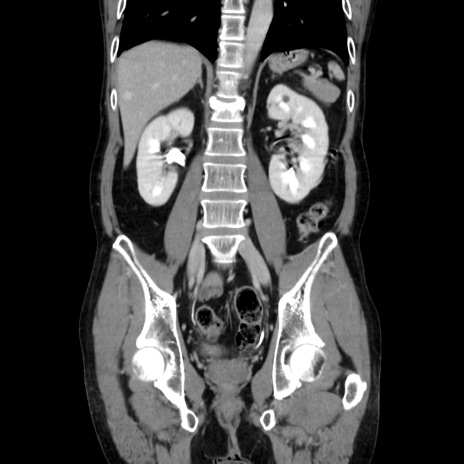

症例37(冠状断像)

【症例】40歳代 男性

【主訴】腹痛

【現病歴】4時間ほど前に電車に乗車中に臍部上より腹痛出現。徐々に増悪し起立困難となり、救急外来受診。生ものは数日食べていない。今朝お雑煮を食べた。

【身体所見】BT 36.8℃、BP 117/84mmHg、HR 91/min、SpO2 97%、苦悶様、腹部:臍上部広範囲圧痛あり、反跳痛±

【データ】WBC 8100、CRP 0.03